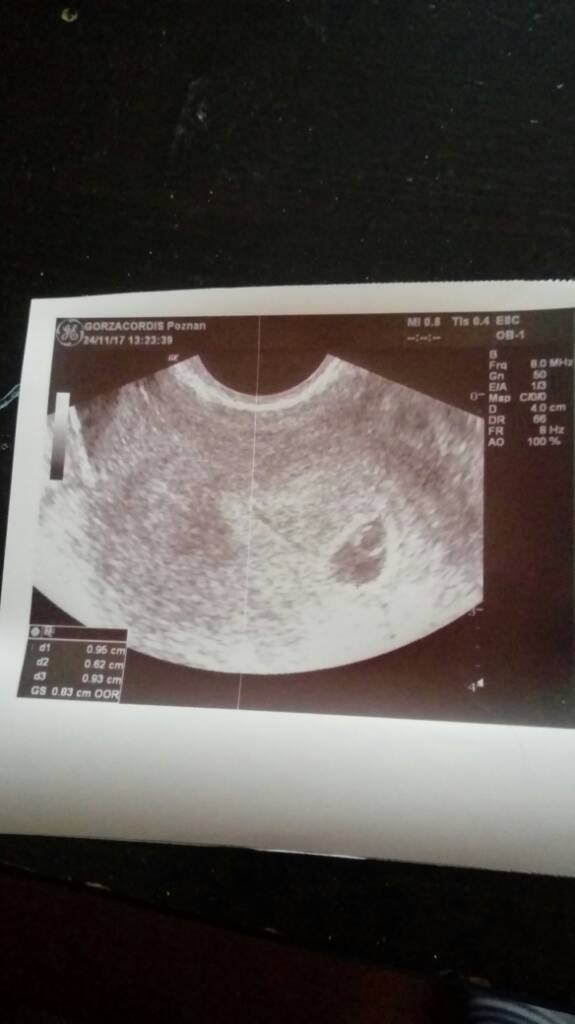

Ja w 6+1 widzialam to:

jakiś zarys zarodka z pikającym białym punkcikiem czyli serduszkiem no i ciałko żółte. Na nastepnej wizycie to chyba filmik zrobię ja albo M :-)